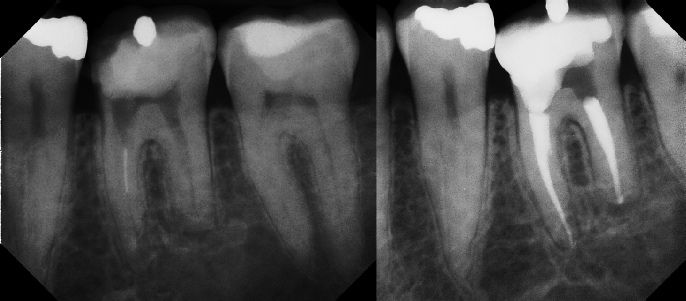

Pre-op Post-op 1 Post-op 2